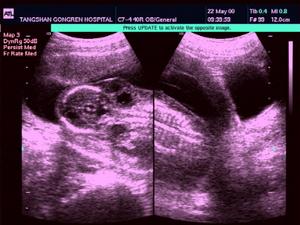

頸部巨大囊狀水瘤的存在,可造成胎兒的娩出困難。一般在出生後即可在頸側部見到軟質的囊性腫塊,有明顯波動感,透光試驗陽性。其界限常不清楚,不易被壓縮,亦無疼痛。腫瘤與皮膚無粘連,生長緩慢,大小無明顯變化。但易並發感染,且較難控制。還可發生囊內出知,此時瘤體驟然增大,張力增高,呈青紫色,壓迫周圍器官可產生相應的症狀。有的可廣泛侵及口底、咽喉或縱隔,壓迫氣管、食管引起呼吸窘迫和咽下困難,甚至危及生命。

頸部囊狀淋巴管瘤1、頸後三角區囊性腫塊,具有向四擊(鎖骨上下、口底、氣管食管旁及縱隔)蔓延生長特點,界限常不清楚。多見於嬰幼兒。出生時即呈巨大,亦可逐漸長大。

2、囊瘤柔軟,一般無壓縮性,能透光。表麵皮膚正常,不粘連。

3、內容物淡黃透明或乳糜狀,偶帶血性。鏡下可見大量含有膽固醇結晶的淋巴細胞。

4、囊瘤較在累及口底、舌或咽部時,可有語言、呼吸或吞咽障礙。囊瘤位於鎖骨上時,可有臂叢受壓出現運動障礙或肌肉萎縮。有時氣管受壓移位。